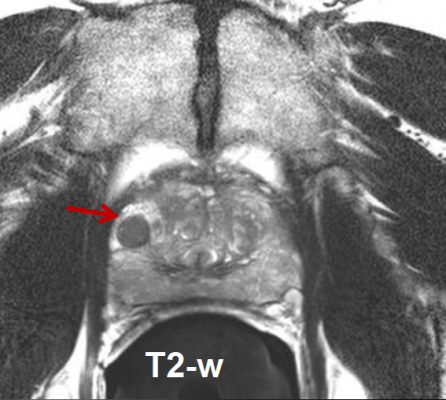

Proton Therapy Center Czech in Prague utilizes the most advanced form of proton therapy scanning available today — in the form of what is simply referred to as pencil beam scanning. This remarkable tool enables tumor treatment with millimeter precision, without damaging to surrounding healthy structures. Additionally all diagnostic methods including positron emission tomography/computed tomography (PET/CT) are available in a single, centralized location. Therefore examinations and planning times are shortened by up to 14 days. It is well established fact that surgery and conventional radiotherapy using photons (X-rays), can cause serious long-term side effects such as erectile dysfunction, loss of fertility, as well as various forms of urinary incontinence, rectal inflammation and bleeding, and intestinal fibrosis. While conventional X-ray radiation unnecessarily exposes up to 50 percent more health tissue to unwanted radiation, protons on the other hand can be precisely focused only upon the tumor without damaging sensitive health organs and tissues around it. Last but not least, the majority of patients are able to maintain their sexual potency.